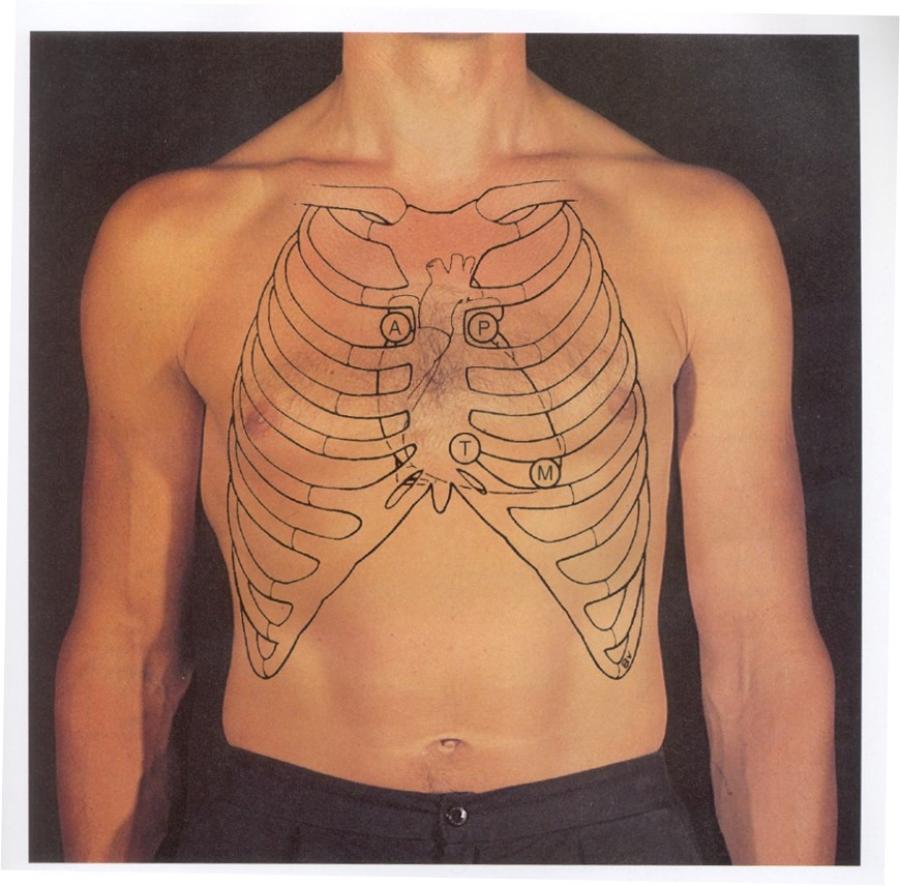

point out these spaces:

R/L 2nd ICS

Erb’s point (where is this?)

Left sternal

border (where is this?)

Left 5th ICS (where is this?)

look at picture

- Erb’s point – left 3rd ICS

- Left sternal border – 4th or 5th ICS

- Left 5th ICS - midclavicular